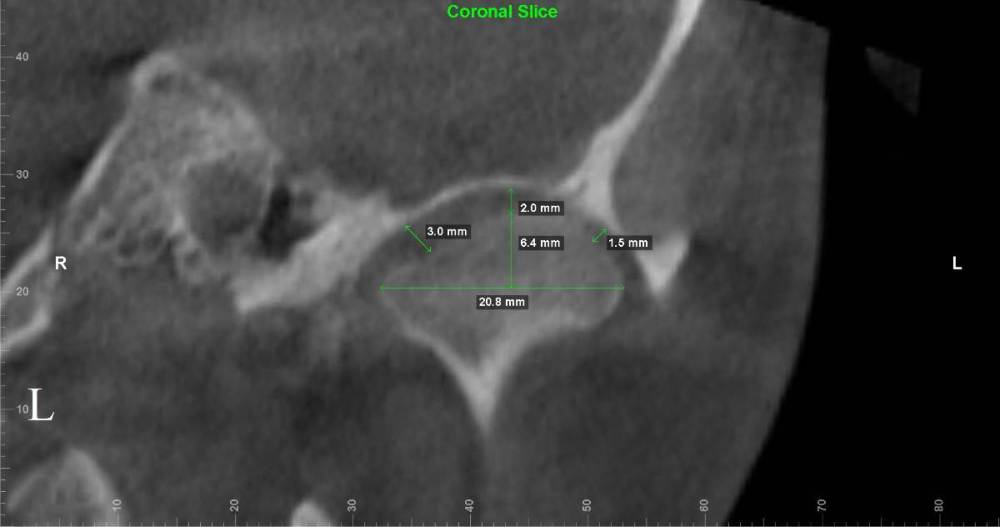

Lotos123 Опубликовано 24 ноября, 2022 Поделиться Опубликовано 24 ноября, 2022 чувствую боль справа и щелчки слева Ссылка на комментарий